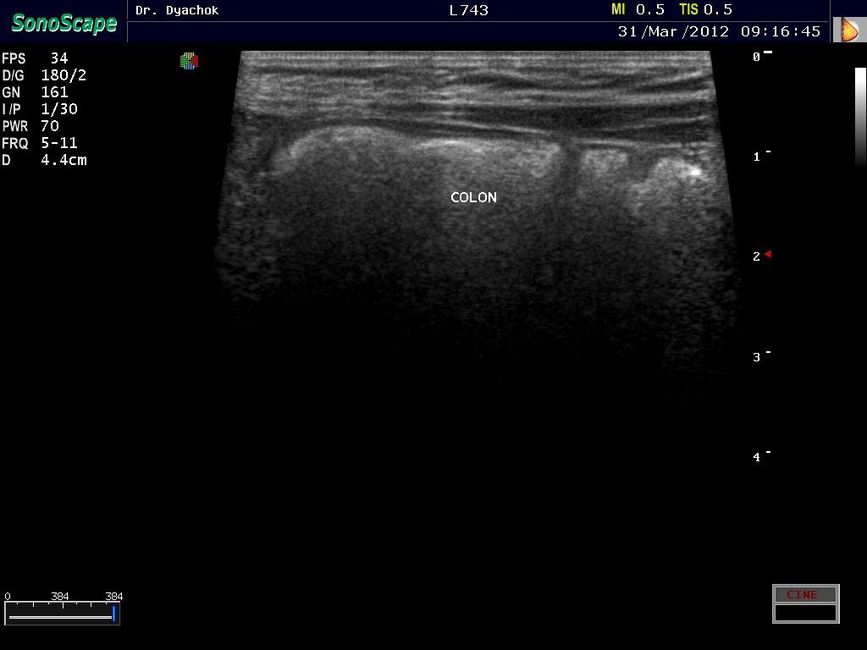

• Исследования поверхностных и абдоминальных органов